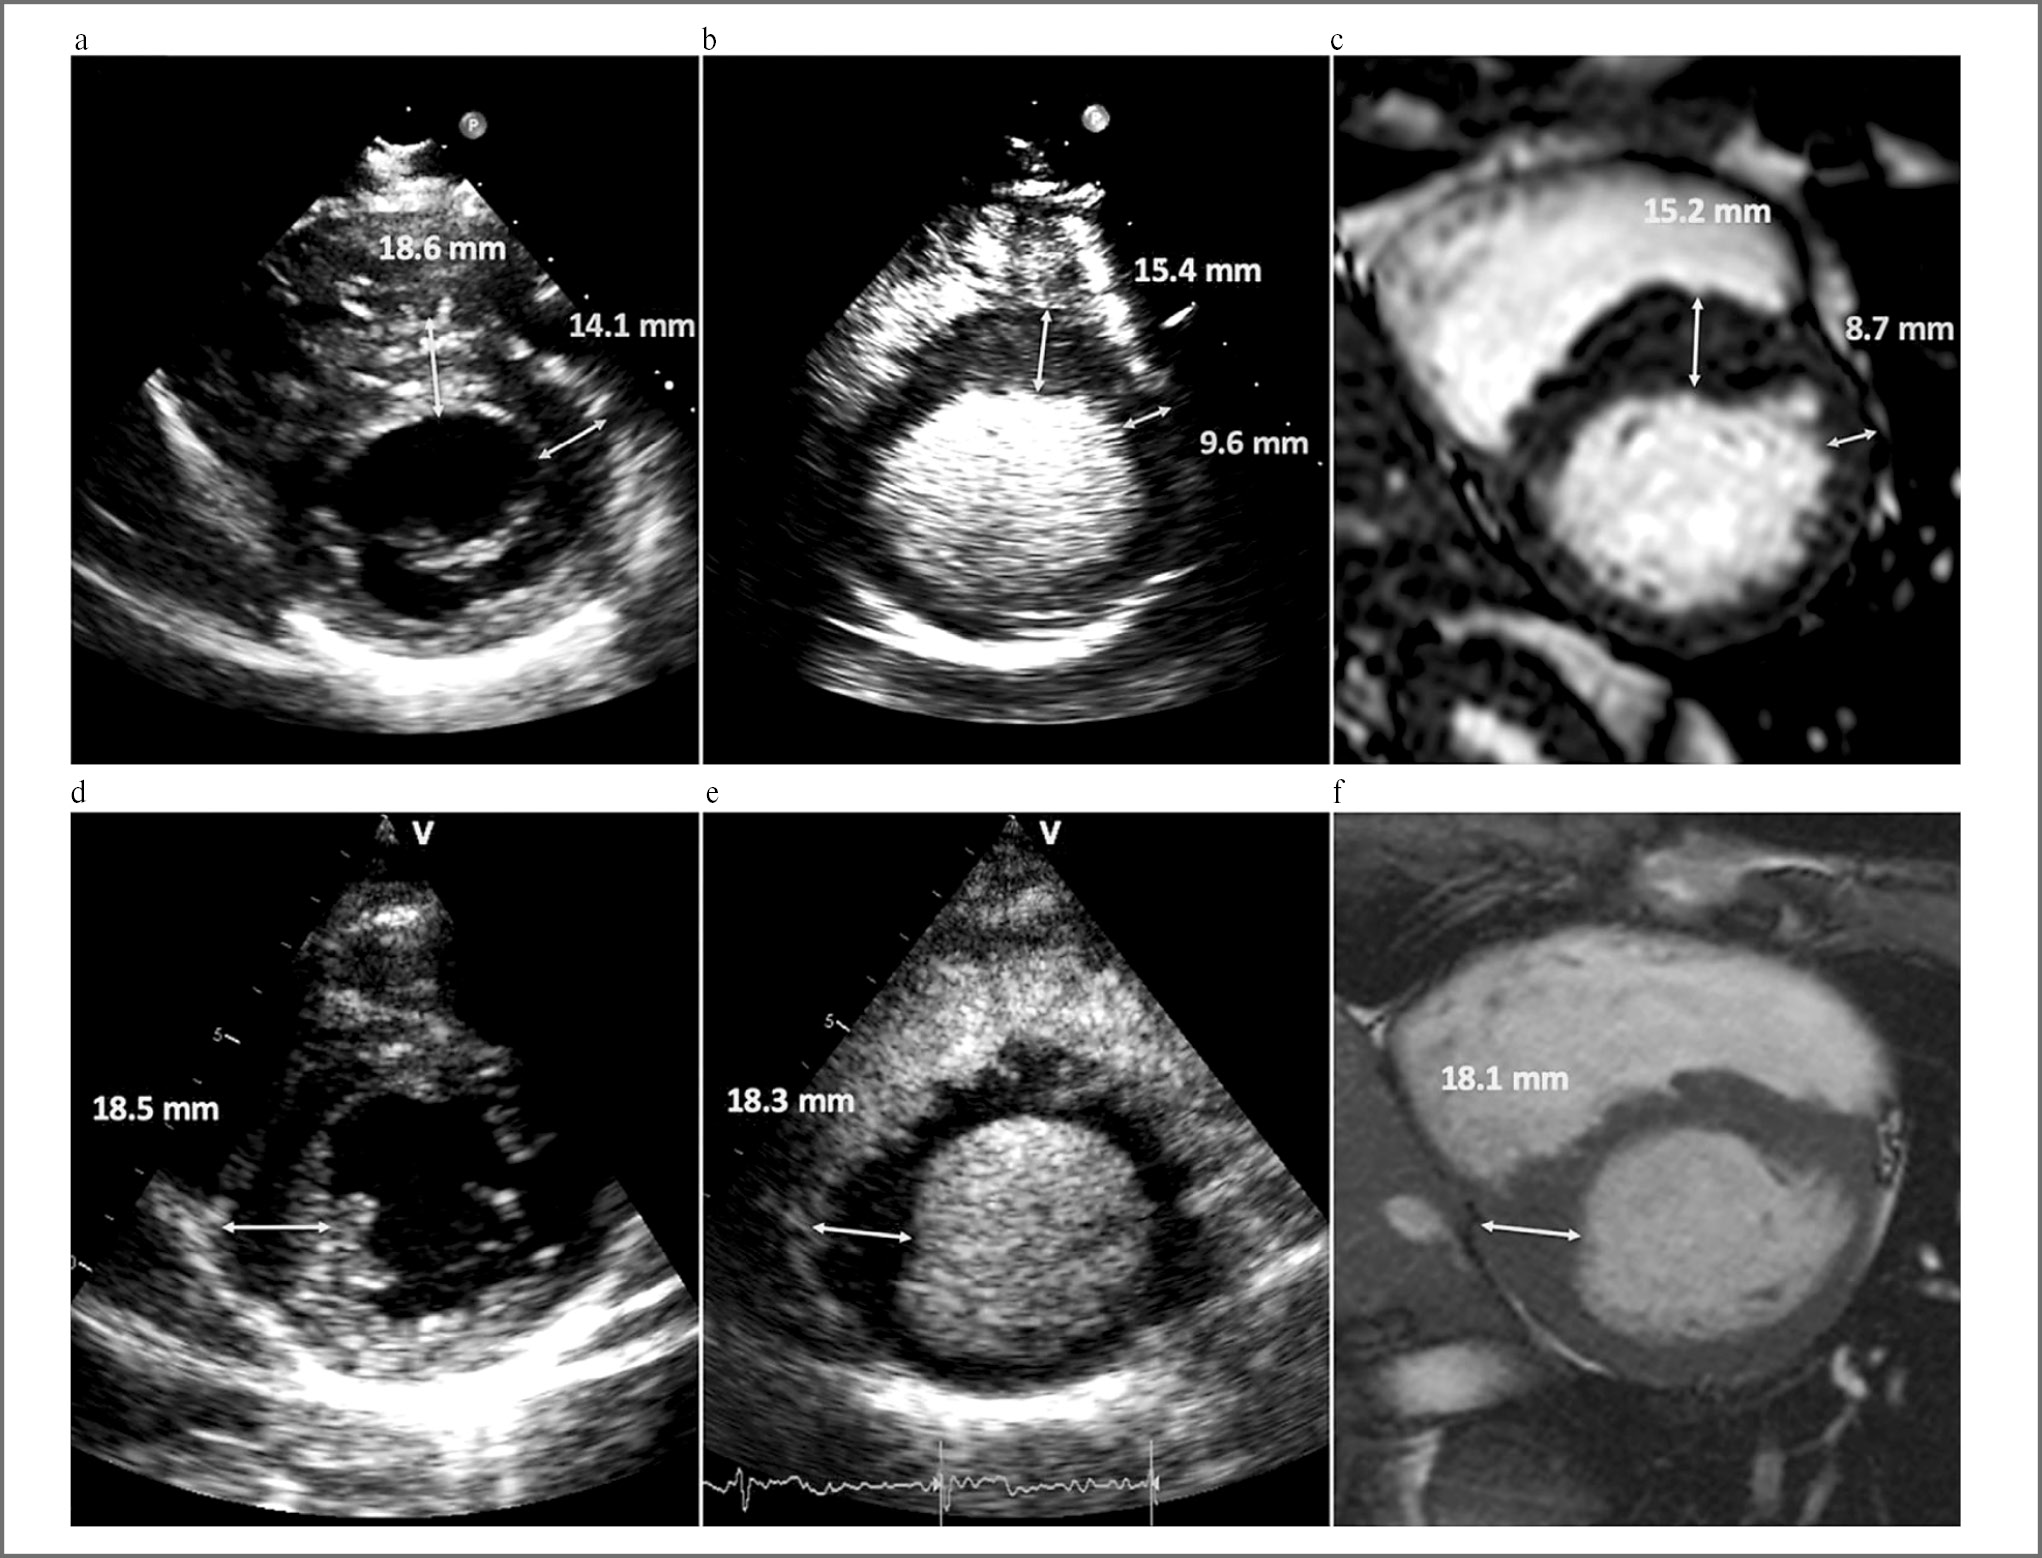

Одним из наиболее перспективных направлений использования контрастирования в ЭхоКГ является контрастирование левого желудочка [19]. Контрастирование полости левого желудочка способно улучшить качество диагностики целого ряда клинических состояний: определение нарушений локальной сократимости, оценка фракции выброса, выявление внутриполостных образований (тромб, миксома), диагностика гипертрофической кардиомиопатии, эозинофильного миокардита, псевдоаневризмы, некомпактного миокарда [19, 26–30]. В некоторых случаях (например, при оценке фракции выброса и функции левого желудочка) чувствительность метода может сравниться с проведением МРТ сердца (рис. 3) [28].

Рис. 3. Сравнение стандартной ЭхоКГ (a, d), контраст-усиленной ЭхоКГ (b, e) и МРТ сердца у пациентов с гипертрофической кардиомиопатией (c, f) [31].

Fig. 3. Comparison of standard EchoCG (a, d), contrast-enhanced EchoCG (b, e) and MRI in patients with hypertrophic cardiomyopathy (c, f) [31].